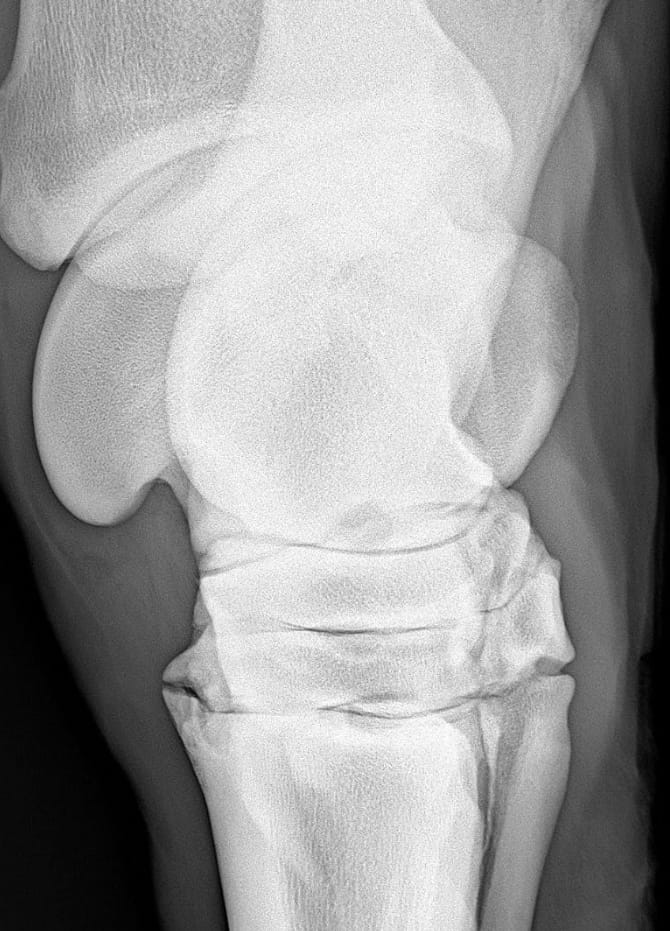

L’artrosi del cavallo è una patologia degenerativa che colpisce le articolazioni e tende a peggiorare con il tempo.

L’artrosi del cavallo è una malattia che provoca un progressivo deterioramento della cartilagine articolare. Questo comporta dolore, rigidità e riduzione della mobilità. È importante sapere che non esistono farmaci o iniezioni in grado di far guarire il cavallo: l’obiettivo deve essere la gestione a lungo termine.